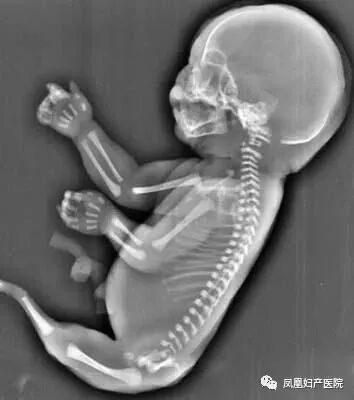

在医学上,有一种罕见的病症叫做美人鱼综合症,胎儿的两条腿紧密结合,看上去就像是美人鱼的尾巴。

27岁的小美(化名)和相爱多年的男友结婚一年后,一个小生命的悄然到来,给整个大家庭送上了一份惊喜,他们俩感觉太幸福了。然而不幸的事情发生了:小美孕25周超声检查发现胎儿下肢无双腿,双下肢合并外形似鱼尾状,这是一种非常罕见的多发性畸形,双下肢合并外形似鱼尾状,俗称“美人鱼综合症”。

去年一位40岁的二胎妈妈在一次常规的产检中,发现胎儿下肢是两个大腿骨, 并行排列 ,小腿骨好像有点交叉 。正常胎儿的下肢是不停地在妈妈肚子里动的, 呈现一个外八字,后来确诊为美人鱼综合症。因为多数患病的新生儿出生后,只能存活几个小时,就算活下来,也要接受多次手术治疗。

美人鱼综合症是一种极其罕见的先天性下肢畸形疾病,患者由于血液循环系统在子宫中没有正常发育,从而导致她们的肾脏和其他器官也没有发育完整,他们可能天生就缺失膀胱、子宫、结肠大部分肾脏等多个器官。美人鱼综合症患病几率与连体婴差不多,但夭折率却高得多,因为大部分婴儿天生缺少肾脏之类的重要器官。

胎儿常见畸形检查图

(多发畸形)